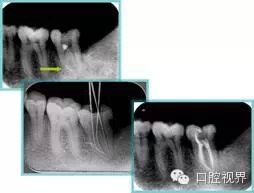

7. 器械折斷

右圖及下圖為器械折斷的 X 線片。箭頭處示折斷器械。

10.webp.jpg11.webp.jpg

解決方法: ( 1 )取出。 ( 2 )通過。 ( 3 )重新確定工作長度,充填。 ( 4 )根尖手術(shù)。

器械折斷可以不用取出,取出的原因多是患者心理因素。留在里面的器械關(guān)鍵是進(jìn)行消毒,預(yù)防性使用抗感染藥物,預(yù)防感染。